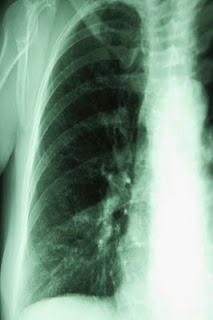

Study after study has shown that standard chest X-rays do not detect early lung cancers. This is true even when X-rays are given on a regular basis to those at high risk for developing lung cancer.

The National Lung Screening Trial (NLST) compared two ways of detecting lung cancer in high-risk smokers: low-dose helical computed tomography (CT) and standard chest X-ray.